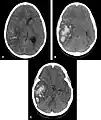

- Hémorragie cérébrale : la principale manifestation clinique de l'angiopathie amyloïde est l'hémorragie intracérébrale de topographie lobaire ou cérébelleuse[7]. La topographie lobaire regroupe les structures corticales et sous-corticale (c'est-à-dire proche de la surface du cerveau). Elle est principalement définie par opposition à la topographie profonde qui englobe essentiellement les ganglions de la base (en particulier le thalamus ou le noyau lenticulaire) et le pont. Cette distinction topographique est importante dans la mesure où l'hémorragie cérébrale lobaire est très évocatrice d'AAC alors que l'hémorragie cérébrale profonde est plutôt évocatrice de microangiopathie hypertensive. Cette distribution reflète l'atteinte préférentielle des petits vaisseaux corticaux dans l'AAC et de artères lenticulo-striées dans l'angiopathie hypertensive[8]. Cependant, parmi l'ensemble des topographies lobaires possibles, l'atteinte du lobe temporal ou occipital semble prédominante, en particulier si le patient avait déjà présenté une hémorragie dans ces régions[9]. Comme pour l'ensemble des AVC, les symptômes associés aux hémorragies cérébrales de l'AAC sont variables. Ils dépendent avant tout de la taille de l'hémorragie et de sa localisation.

Scanner cérébral objectivant une hémorragie lobaire temporale droite évocatrice d'une possible angiopathie amyloïde

Scanner cérébral objectivant une hémorragie profonde (thalamique gauche) plutôt évocatrice d'une angiopathie hypertensive